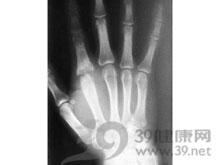

急性化脓性关节炎多见于膝、髋、肩、肘诸关节。发生于婴幼儿者往往与干骺端的骨髓炎有密切关系。但亦有不少病例是通过血运侵入关节滑膜而引起的,最后也可破坏骨骺而继发骨髓炎。